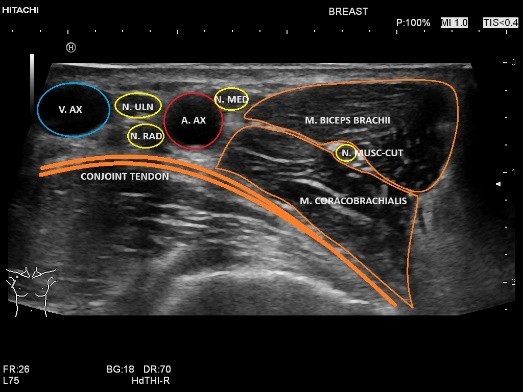

- Echografie van de zenuwen en AI:

In deze presentatie heb ik behandeld wat er nodig is voor degelijk echografisch onderzoek van de zenuwen. Een nauwgezette kennis van de anatomie en het kennen van de anatomische landmarks is een pré. Dit is getoond door de anatomie van de bovenste extremiteiten te laten zien en daarbij de onderzoeksmethode. Vanuit hier heb ik de raag gesteld waar AI ons vandaag de dag tegemoet kan komen middels de ontwikkelingen die er zijn. Zo kan AI de zenuwen herkennen en de overige weke delen, zoals spieren afgrenzen. AI kan bij dynamisch onderzoek de zenuw vervolgen en nauwkeurig een CSA meting doen. Daarnaast heb ik casuïstiek behandeld steeds in het licht van AI, met daarbij de vragen: is AI instaat bij verstoorde anatomie de zenuw te herkennen, herkent AI de pathologie zoals beknelling om compressiefactoren, zoals anatomische variatie en waar ligt het verschil/verantwoording van echografist en AI. Dat AI toekomst heeft is evident, deze ontwikkeling hou je niet tegen. Aan ons om steeds weer AI te controleren en ons voordeel er mee te doen.